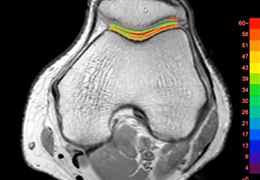

Using MR data with different TE and spin lock times, this protocol measures T2, T2*, or T1rho values of the specified ROI and shows color maps.